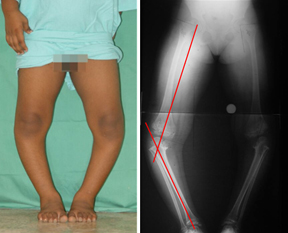

Clinical picture and full length xray not only help in identifying the seat of deformity and any other deformities which may be masked, but also help in planning the kind and amount of correction, the overall biomechanics of the limb and also serve as a reference for future follow ups.

Here in this particular patient the deformity is only in the proximal tibia (the leg bone close to knee), albeit on both the sides.